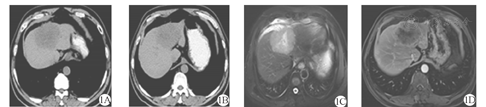

患者 男,57岁,乙型肝炎病史20余年。患者以"右上腹不适1周"为主诉入院。上腹部平扫CT(2015年10月21日)示:肝内Ⅳ段及Ⅷ段交界处可见8.2 cm × 6.2 cm团片状低密度区(图1A、图1B)。上腹部增强MRI(2015年10月22日)示肝左叶团块影,增强扫描病灶边缘不规则强化(图1C、图1D)。实验室检查:乙型肝炎表面抗原(HBsAg)阳性,甲胎蛋白(AFP)833.40 μg/L,癌抗原(CA)19-9 108.58 kU/L,肝功能Child-Pugh分级B级。临床诊断为原发性肝细胞癌,巴塞罗那肝癌分期(BCLC)B期。患者无介入治疗禁忌证,于2015年10月29日行肝动脉化疗栓塞术(TACE),术中造影见肝内肿瘤轻度染色(图2A),超选后肝右动脉予以碘化油5 ml +吡柔比星5 mg缓慢栓塞,辅助明胶海绵微粒(350~560 μm)50 mg+吡柔比星10 mg栓塞至肿瘤染色消失(图2B)。为明确病理诊断,术中经皮经肝超声定位下穿刺活检(16 G COOK活检针),术后病理(图3):肝细胞癌。术后第4天复查:AFP 263.50 μg/L,CA19-9 233.4 kU/L,肝功能基本正常。1个月后复查:AFP 712 μg/L,CA19-9 512.3 kU/L。于是,2015年12月7日再次行TACE,术中造影见肝肿瘤轻微染色(图4A),予以50 mg明胶海绵微粒(350~560 μm)10 mg+雷替曲塞2 mg+奥沙利铂50 mg栓塞肿瘤,造影见肿瘤染色消失(图4B)。第1次TACE术后1个月(2015年12月10日)复查上腹部CT示肝内见团片状、点状高低混杂密度影,较大切面为7.3 cm × 6.2 cm,局部突出于肝包膜之外,腹膜及肝被膜下见多发小结节状影,提示腹膜转移(图5A、图5B)。第1次TACE术后3个月(2016年2月14日)复查上腹部CT示肝内病灶较前缩小,腹膜多发结节状较前增多、增大(图5C);复查AFP上升至6 028 μg/L,腹水脱落细胞检查为腺癌。为控制腹膜转移瘤进展,患者口服索拉非尼(200 mg/次,2次/d)和腹腔灌注化疗(每3周腹腔灌注洛铂、雷替曲塞、香菇多糖及苦参碱)。第1次TACE术后6个月(2016年5月14日)复查上腹部CT提示肝内病灶缩小,坏死明显,但腹膜转移灶较前增多、增大,腹水较前增多(图5D);复查AFP >10 000 μg/L。患者于2016年6月20日不慎摔倒出现意识模糊伴发恶心呕吐,呕吐物为咖啡样物,随后出现心脏、呼吸骤停,临床死亡。

注:1A和1B:肝内Ⅳ段及Ⅷ段交界处可见8.2 cm × 6.2 cm团片状低密度区,边界不清,密度欠均匀,中心可见坏死液化区;1C:上腹部MRI示肝内团块状稍长T2信号影,8.0 cm × 7.0 cm;1D:增强扫描示病灶边缘不规则明显强化,内部见斑片状未强化区